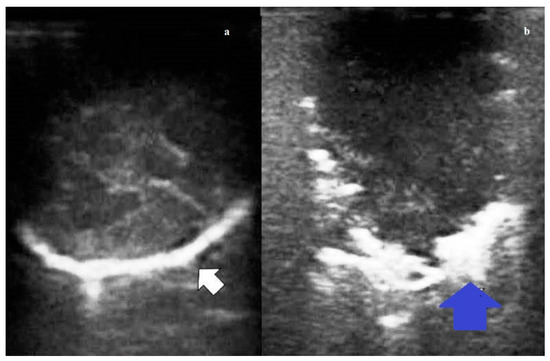

The identification of 40/131 (30.53%) nodules was allowed by TUS. All the nodules identified on TUS were peripherally located and adherent to the parietal pleural surface. The sonographic pattern of nodules on TUS was characterized by a greater appearance of jagged margins (82.50% versus 52.50%, p = 0.004), hyperechoic pattern (32.50% versus 10.00%, p = 0.01) and hyperechoic striae (40.00% versus 12.50%, p = 0.005) compared to ILU (Figure 3). On TUS, we did not record any statistically significant differences in terms of shape, margins and echogenicity between primary benign and malignant lung nodules and metastasis (Table 4).

In previously published data, nodules characteristics at ILU have been shown to correlate with probability of malignancy [16,24,25]. Similarly, in the present study a malignant lesion seemed to be indicated more by an irregular shape and the presence of jagged margins rather than by well-defined rounded margins. This morphological differentiation was not possible by TUS examination, where the more air-filled periphery of the nodule is known to create ultrasound artifacts at the interface with the healthy aerated lung parenchyma resulting in irregular and blurred deep margins. On the contrary, the echographic pattern (i.e., hypoechoic or hyperechoic appearance) and the presence of hyperechoic spots within the lesion at ILU were not shown to present any correlation in terms of histology between benign and malignant lesions. On TUS evaluation, a hyperechoic pattern and the presence of hyperechoic striae have been observed more than on ILU, suggesting that these images are probably the result of the difference in acoustic impedance that ultrasound comes to find at the interface between the aired lung content and soft tissues of the chest wall. Another possible explanation lies in the interposition of also few microns of air between the nodule and the probe due to an incomplete adherence of the lesion to the parietal pleura [30]. When the acoustic attenuation of the chest-wall structures is removed and the probe is directly placed on lung parenchyma (as during ILU examination), the reflection phenomena of the ultrasound beam are reduced and a hypoechoic appearance for lung nodules results increased. A hyperechoic pattern and the presence of hyperechoic striae on ILU examination can be still explained by an inhomogeneous tissue composition between different areas within the nodule. This suggestion needs to be carefully evaluated and requires further study to be confirmed. Obviously, more detailed data on the morphology of pulmonary nodules are pre-operatively provided from CT and PET scans. However, despite the characterization of the lung nodules at ILU not having a strictly clinical value, it can help in better understanding the influences that the pulmonary air content and the elevated difference in acoustic impedance generated at the interface with the overlying soft tissues of the chest wall have in the transthoracic study of pulmonary diseases. This allows, at the same time, a more correct interpretation of ultrasound artifacts.

Figure 2. (a) Intraoperative lung ultrasound (ILU) scan showing a hyperechoic pulmonary nodule (white arrow) with a regular rounded shape and well-defined margin. The final histological diagnosis was pulmonary hamartoma. (b) Intraoperative lung ultrasound (ILU) scan showing a hypoechoic nodule (blue arrow) with irregular shape and jagged margin. The final histological diagnosis was pulmonary adenocarcinoma.